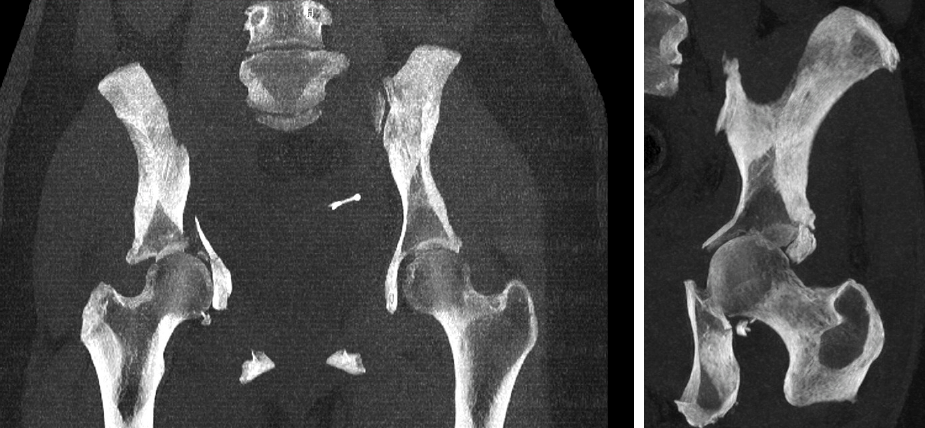

FRACTURA DE PELVIS Y ACETÁBULO

La pelvis conecta la columna con las piernas y soporta el peso del cuerpo. Puede fracturarse por traumatismos graves o por osteoporosis.

El acetábulo es la parte de la pelvis que forma la cavidad donde encaja la cabeza del fémur, formando la articulación de la cadera.

Algunas fracturas sanan con reposo, pero otras necesitan cirugía.

FRACTURA DE CADERA

Las fracturas de cadera (fémur proximal) son frecuentes en personas mayores tras caídas.

La opciones de tratamiento pueden ir desde la osteosíntesis (fijar los huesos con clavos, tornillos o placas) a la prótesis de cadera, dependiendo del tipo de fractura (subcapital, pertrocantérea, subtrocantérea)